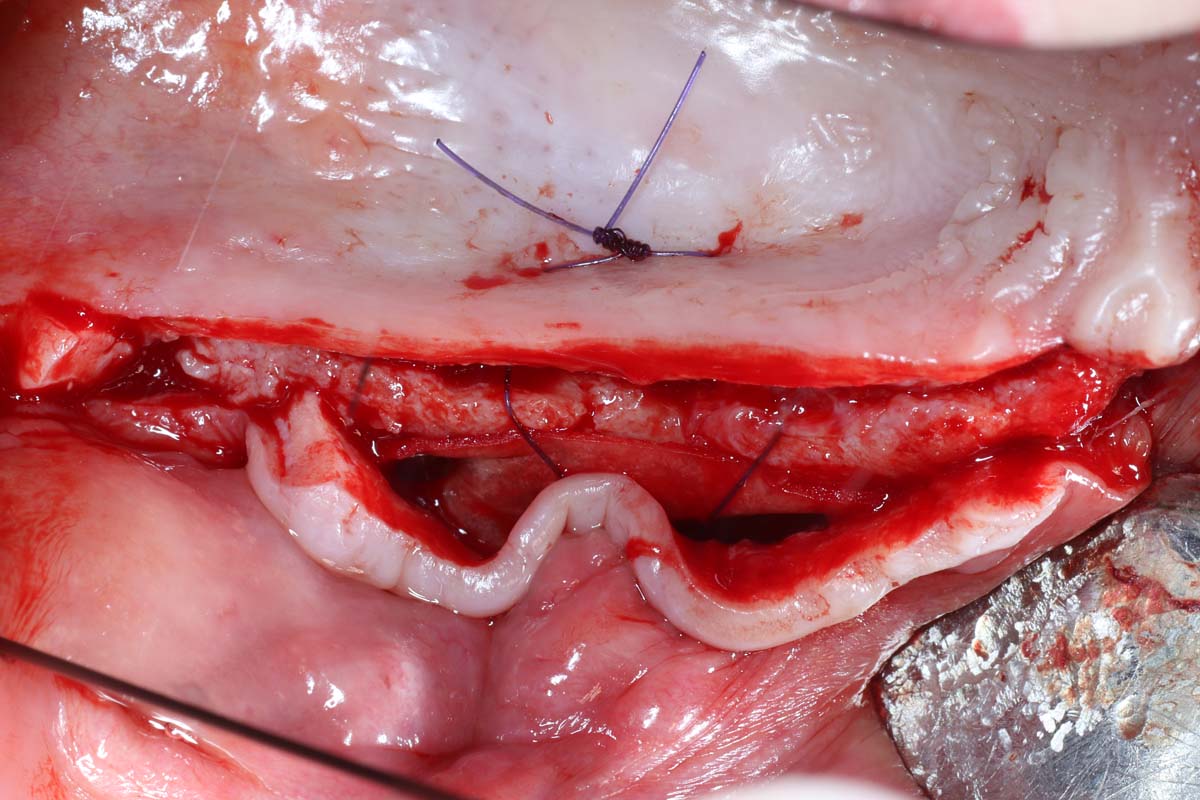

Gain Hands-On Skills and Watch Live Surgery to Master Implant Site Development Techniques

Elevate your skills in implant site development with hands-on practice and live surgical demonstrations. Observe procedures in real time and participate in practical sessions to build confidence in essential techniques, from bone grafting to soft tissue management.

- Indications and step by step surgical protocol for sinus bone grafting – lateral and crestal approach.

- Comprehensive recognition, management, and treatment of intraoperative, early and late postoperative complications.